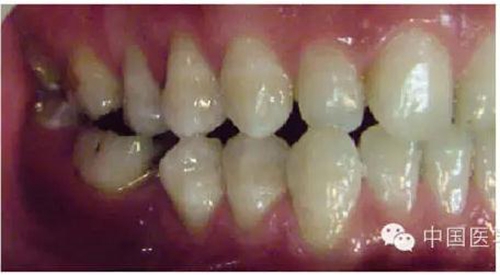

這種咬合接觸的結(jié)果是局部的咬合力集中在凸點接觸的位置,不能被有效分散,可造成受力部位牙體、牙周組織的應(yīng)力集中。最常見的表現(xiàn)是后牙頰舌向呈對刃關(guān)系,另外還常見于不完全遠(yuǎn)中關(guān)系或不完全近中關(guān)系的情況,此時從近遠(yuǎn)中方向來看,上下后牙牙尖之間凸凸相對(圖3)。

圖3 后牙凹凸接觸關(guān)系